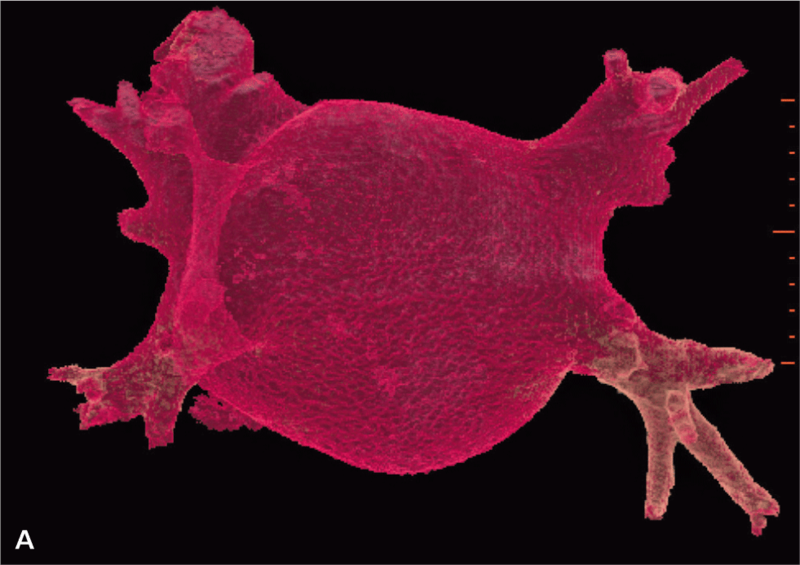

Po operacji wykonano kontrolne badanie TK serca, w którym nie stwierdzono zmian ogniskowych i zagęszczeń zapalnych w uwidocznionym miąższu płucnym. Przełyk oraz pozostałe uwidocznione badaniem struktury śródpiersia również były bez zmian. Uwidocznione węzły chłonne nie były powiększone. Badanie wykazało stan po plastyce przedsionka lewego oraz wszczepieniu sztucznego pierścienia w pierścień zastawki mitralnej. Objętość przedsionka po zabiegu wynosiła 129 cm3 (przed zabiegiem 186 cm3) (ryc. 1A, B, 2A, B).

RYCINA 2. Rekonstrukcja objętościowa (VR transparent) lewego przedsionka. [A] Przed operacją. [B] Po operacji.